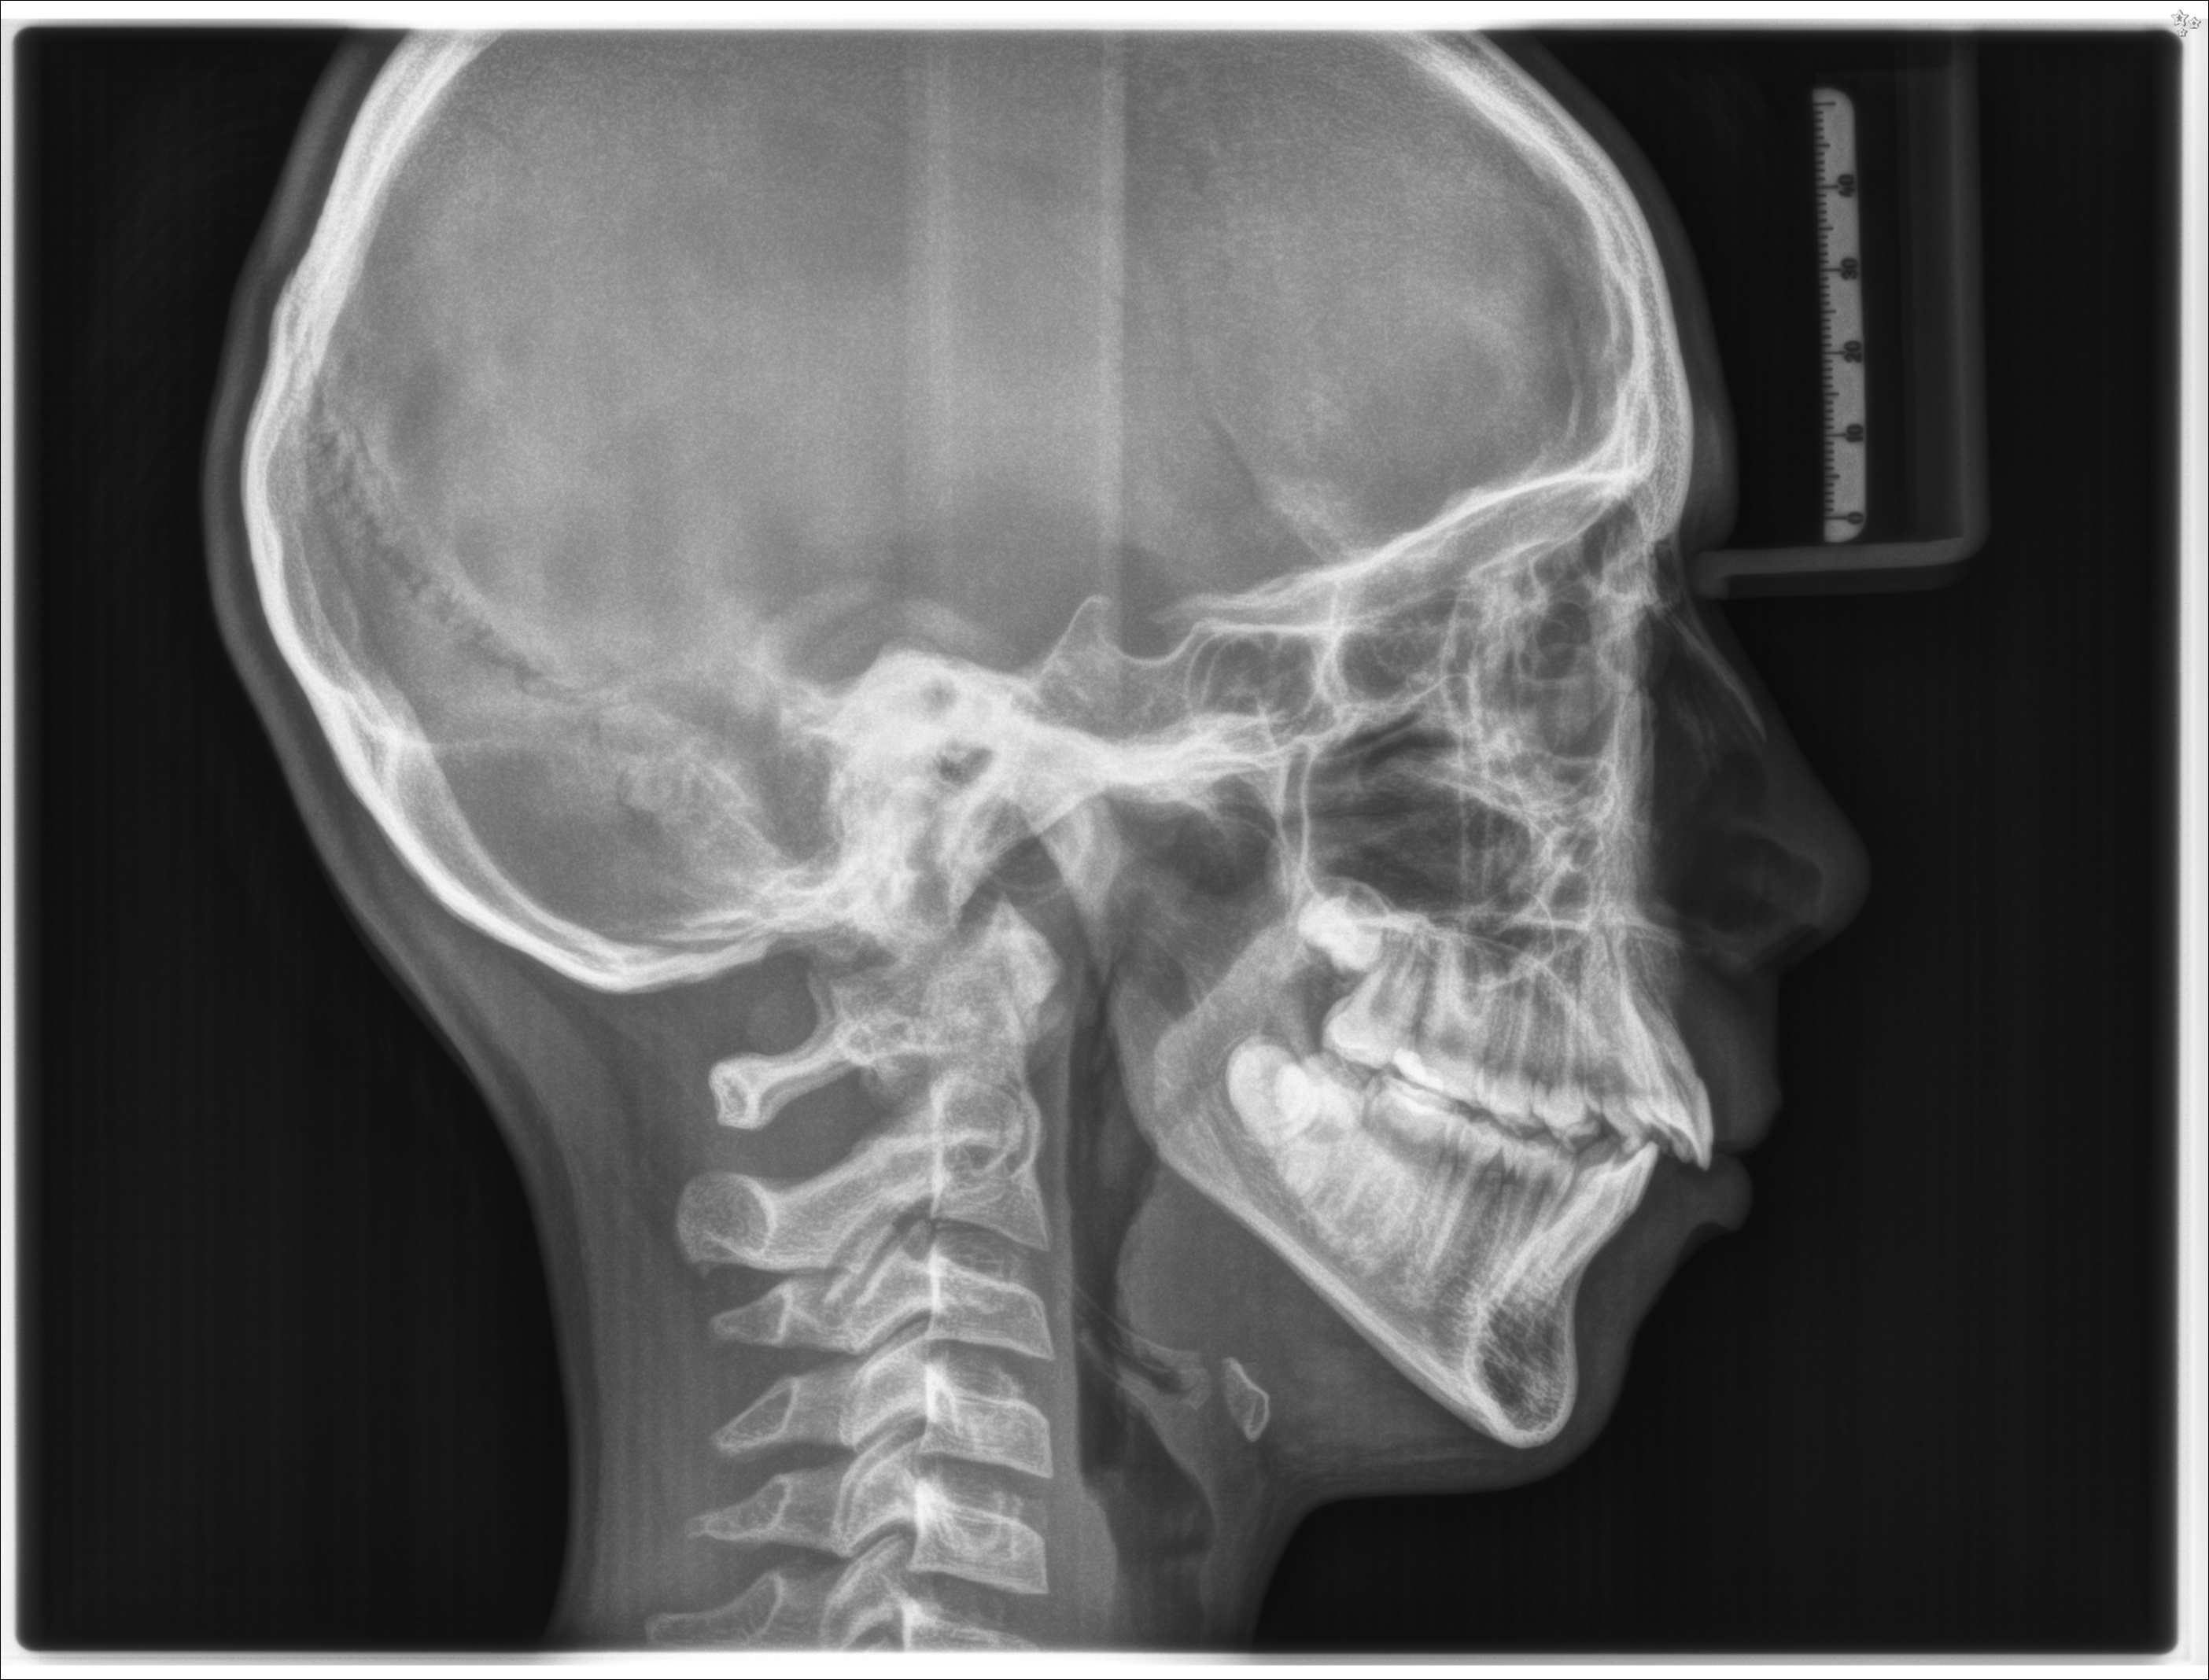

TELERADIOGRAFIA LATERALE DEL CRANIO. 26/10/2019.

Il ragazzo presenta una molocclusione di seconda classe scheletrica. É un soggetto iperdivergente con tipologia di crescita iperdivergente, l'incisivo superiore è vestiboloposto e vestiboloinclinato, l'incisivo inferiore è linguoposto e linguoinclinato.

TELECRANIO

La radiografia che riprende il cranio del paziente di lato viene chiamata dagli specialisti TELECRANIO. Risulta necessaria in alcuni casi per una corretta diagnosi e per lo studio del caso clinico.